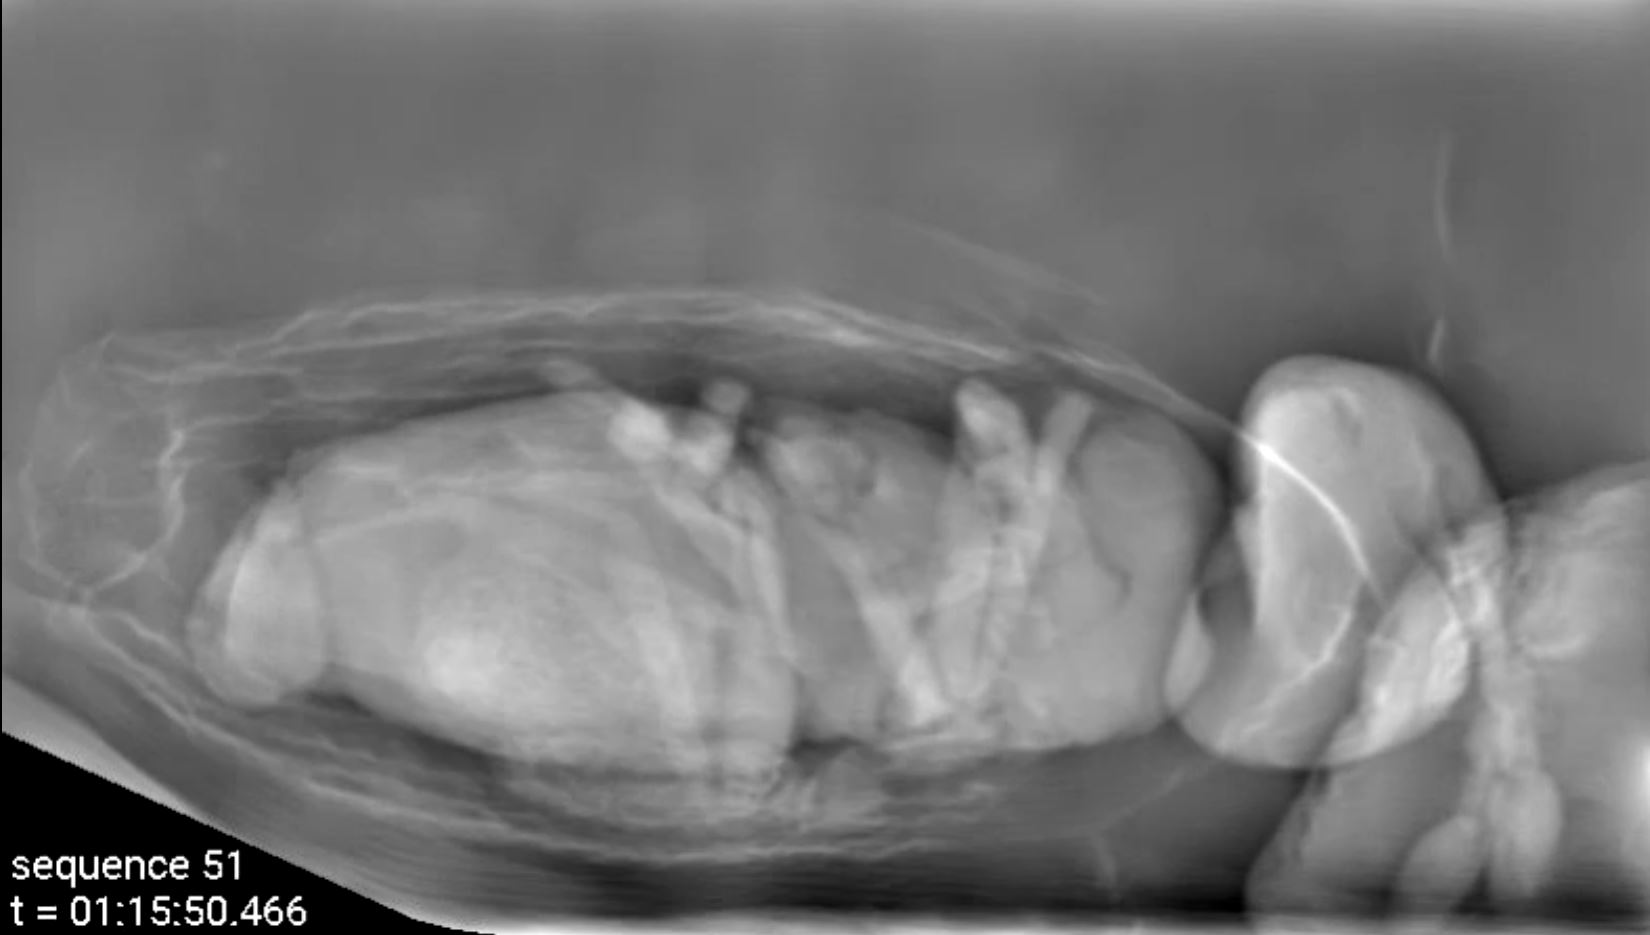

Durch die Kombination von propagationsbasiertem Röntgen-Phasenkontrast mit dem Bragg-Mikroskop und dem photonenzählenden Detektor, alle für eine Röntgenenergie von 30 Kilo-Elektronenvolt (keV) optimiert, erreicht das Verfahren nahezu die maximal mögliche Dosiseffizienz für Röntgen-Phasenkontrast. Dies gestattet wiederum deutlich längere Beobachtungszeiten bei einer mikrometergenauen Bildauflösung kleiner lebender Organismen. Gemeinsam mit Wissenschaftlerinnen und Wissenschaftlern aus ganz Deutschland demonstrierten die Forschenden das Verfahren in einer Pilotstudie an winzigen parasitischen Wespen. Mehr als 30 Minuten lang beobachteten sie jeweils die Wespen in ihren Wirtseiern und wie sie sich aus diesen befreien. „Die Methode eignet sich auch für biomedizinische Anwendungen, beispielsweise zur schonenden dreidimensionalen histologischen Untersuchung von Proben bei Biopsien“, sagt Spiecker. In Zukunft wollen die Forschenden den Aufbau weiter verbessern, um beispielsweise das Gesichtsfeld zu vergrößern und die mechanische Stabilität für noch längere Messungen weiter zu steigern.